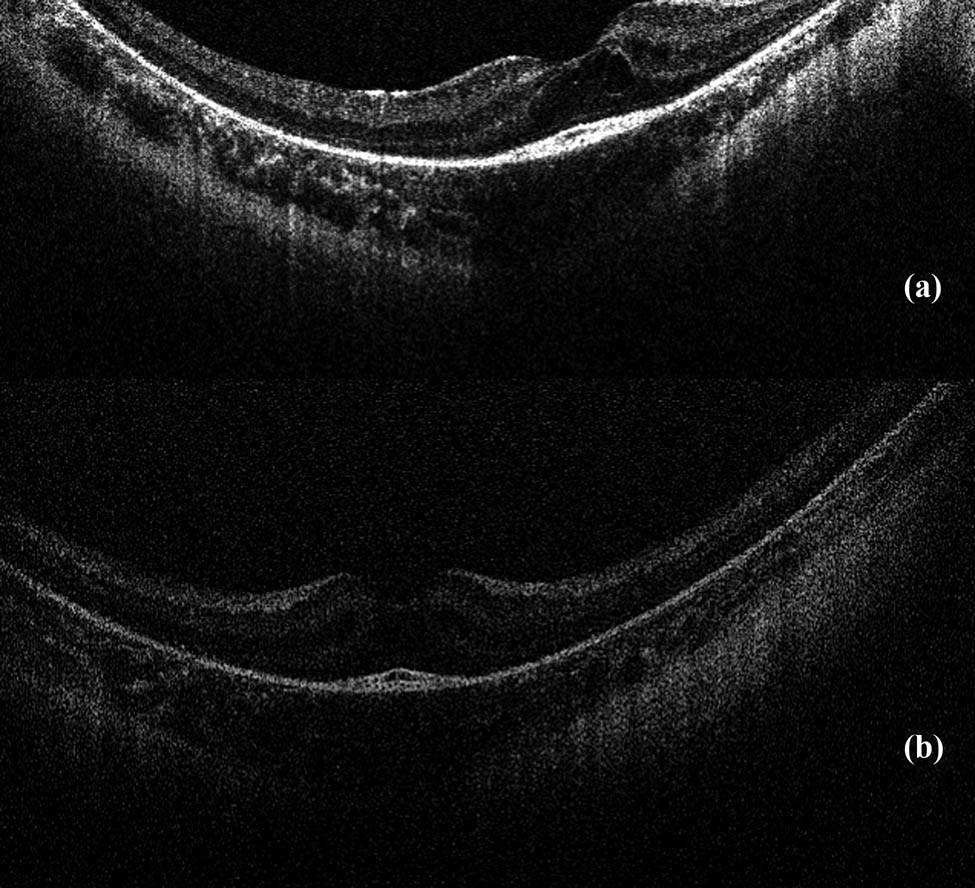

The child was born by spontaneous delivery, at the 38th week of pregnancy with low birth weight −2,300 g. An echocardiographic examination was performed on the second day of life due to abnormal heart murmur. The examination showed atrial and ventricular septal defect and aortic coarctation. Some distinct features that draw attention to the girl are microcephaly, micrognation, facial dysmorphism: a prominent nasal bridge, thick hair and eyebrow, abnormalities of the palpebral fissures (downslanting and almond-shaped palpebral fissures) [Figure 2], prominent upper incisors and small and short hands [Figure 3]. During the first weeks of life, the patient developed larynx flaccidity and chronic neutropenia causing compromised immunity. At the ophthalmology department, the girl underwent a full ophthalmological examination, which was performed under short, inhalation anesthesia due to the patient’s failure of cooperation. Visual acuity was impossible to assess because of difficult contact with the child. Eyeball movement was normal, and no nystagmus was found. Refraction after accommodation paralysis revealed high myopic astigmatism: right eye −0.5 Dsph to −6.25 Dcyl ax 178 and left eye −3.25 Dsph to −4.5 Dcyl ax 180. The anterior segment was within normal limits in the slit lamp examination. Ophthalmoscopic examination of both eyes demonstrated pale optic discs and “salt and pepper” retinopathy, accompanied by arterial stenosis [Figure 4]. The intraocular pressure in the right eye was 12 mm Hg and in the left was 10 mm Hg. The axial length of both eyeballs was similar, i.e., in the right eye was 20.63 mm and in the left was 19.40 mm. The central thickness of cornea in the right eye was 413 µm and in the left was 439 µm. Handheld optical coherence tomography revealed macular edema in both eyes [Figure 5]. Electroretinography showed a reduced response amplitude of cones and rods [Figure 6].

(a) and (b) Results of optical coherence tomography – macular edema in both eyes.

Regarding lesions located in the macula, Beck et al. [9] presented a case of nonleaking cystoid macular edema in an 11-year-old patient with Cohen syndrome. Uyhazi et al. [3] focused on the analysis of the initial modification that occurs in the structure of the retina in the course of this syndrome. The authors described the case of a 13-month-old girl in whom OCT revealed loss of the interdigitation signal between the photoreceptor outer segments and the apical retinal pigment epithelium. Loss of only the photoreceptor outer segments was also noted, suggesting that these are the first visible symptoms of retina that later lead to macular edema and retinal dystrophy characteristic of Cohen syndrome.

Mutation of the VPS13B gene causes an incorrect function of the Golgi apparatus membrane protein, which affects, among others, the function of retinal photoreceptors [3,9,13]. It is assumed that the edema of the macula does not occur due to fluid accumulation, or an increase in vascular permeability, but only because of the impaired adhesion and splitting of several retinal layers [3,9,13]. The macular edema in hereditary retinal dystrophies is caused by a similar mechanism resulting from mutations in individual genes [13].

Bilateral macular edema was confirmed in the patient in handheld OCT. Macular lesions in Cohen syndrome have been reported in the literature, but only in two cases, a characteristic picture of OCT macular edema has been documented [3,9]. It can be assumed that this was due to the lack of access to this study technique in the past.